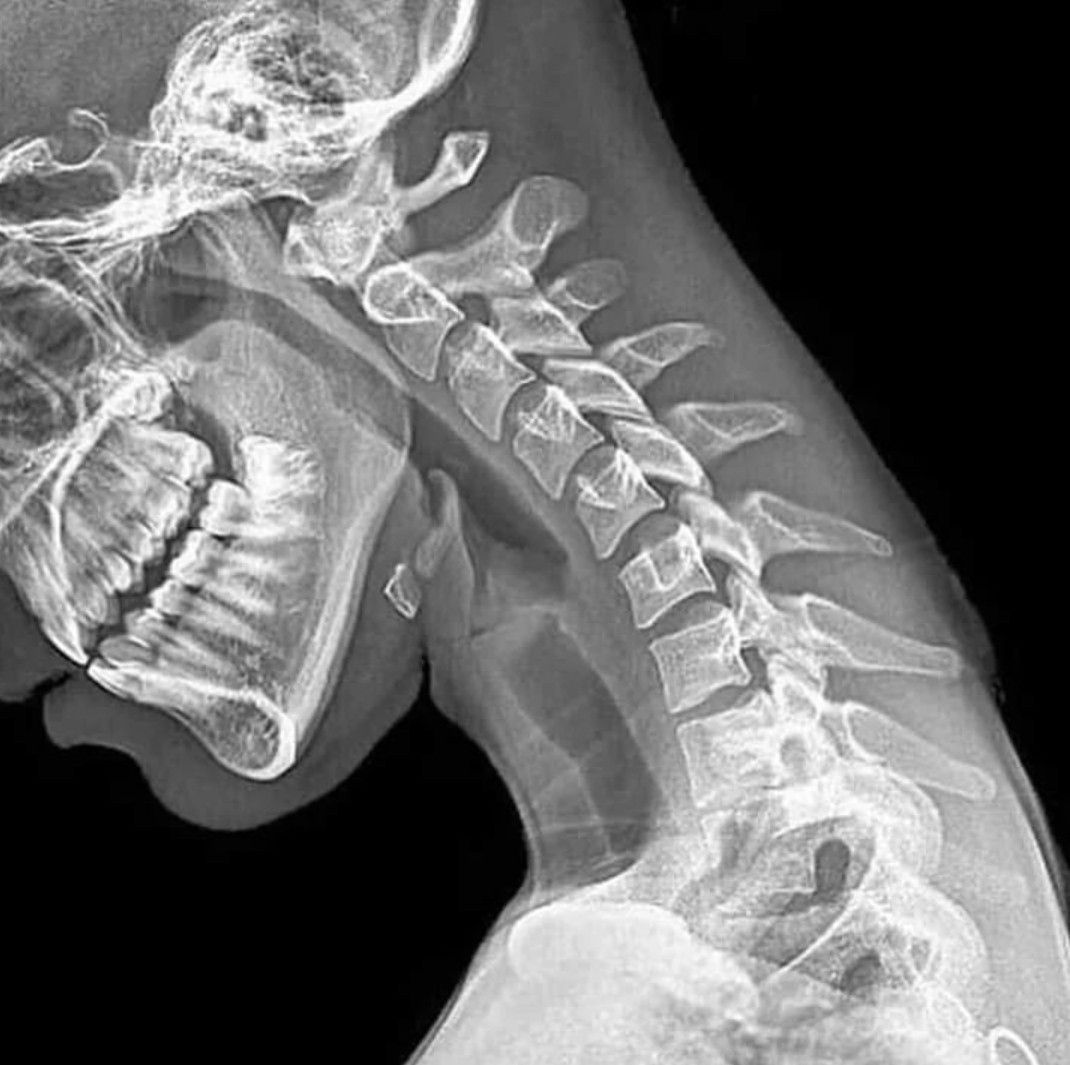

What your cervical spine looks like while being on your phone too much and texting your gf/bf ! It's diagnosed as "Text Neck" Text neck is the term used to describe the neck pain and damage sustained from looking down at your cell phone, tablet, or other wireless devices too frequently and for too long.